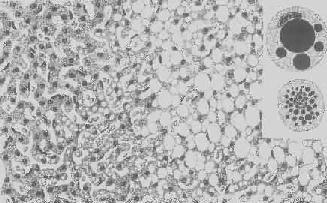

肝细胞气球样变

图1-17 肝细胞气球样变

病毒性肝炎时,肝细胞明显肿胀,胞浆疏松呈气球样

形态学:轻度肝脂肪变性时,肝肉眼观可无明显改变,或仅轻微黄染。如脂仿变性比较显著和广泛,则肝增大,色变黄,触之质如泥块并有油腻感。镜下,肝细胞内的脂肪空泡较小,起初多见于核的周围,以后变大,较密集散布于整个胞浆中,严重时可融合为一个大空泡,将细胞核挤向胞膜下,状似脂肪细胞(图1-18)。脂肪变性在肝小叶中的分布与其病因有一定的关系,例如肝淤血时,小叶中央区缺氧较重,故脂肪变性首先在此处发生。但长期淤血后,小叶中央区的肝细胞大多萎缩、变性或消失,于是小叶周边区肝细胞也因缺氧而发生脂肪变性。磷中毒时,肝细胞脂肪变性则主要发生于小叶周边区,这可能是由于此区肝细胞对磷中毒更为敏感的缘故。

肝细胞脂肪变性

图1-18 肝细胞脂肪变性

肝细胞胞浆内出现大小不等的脂肪空泡;右上角为饿酸染色的脂肪细胞, 脂滴染成黑色